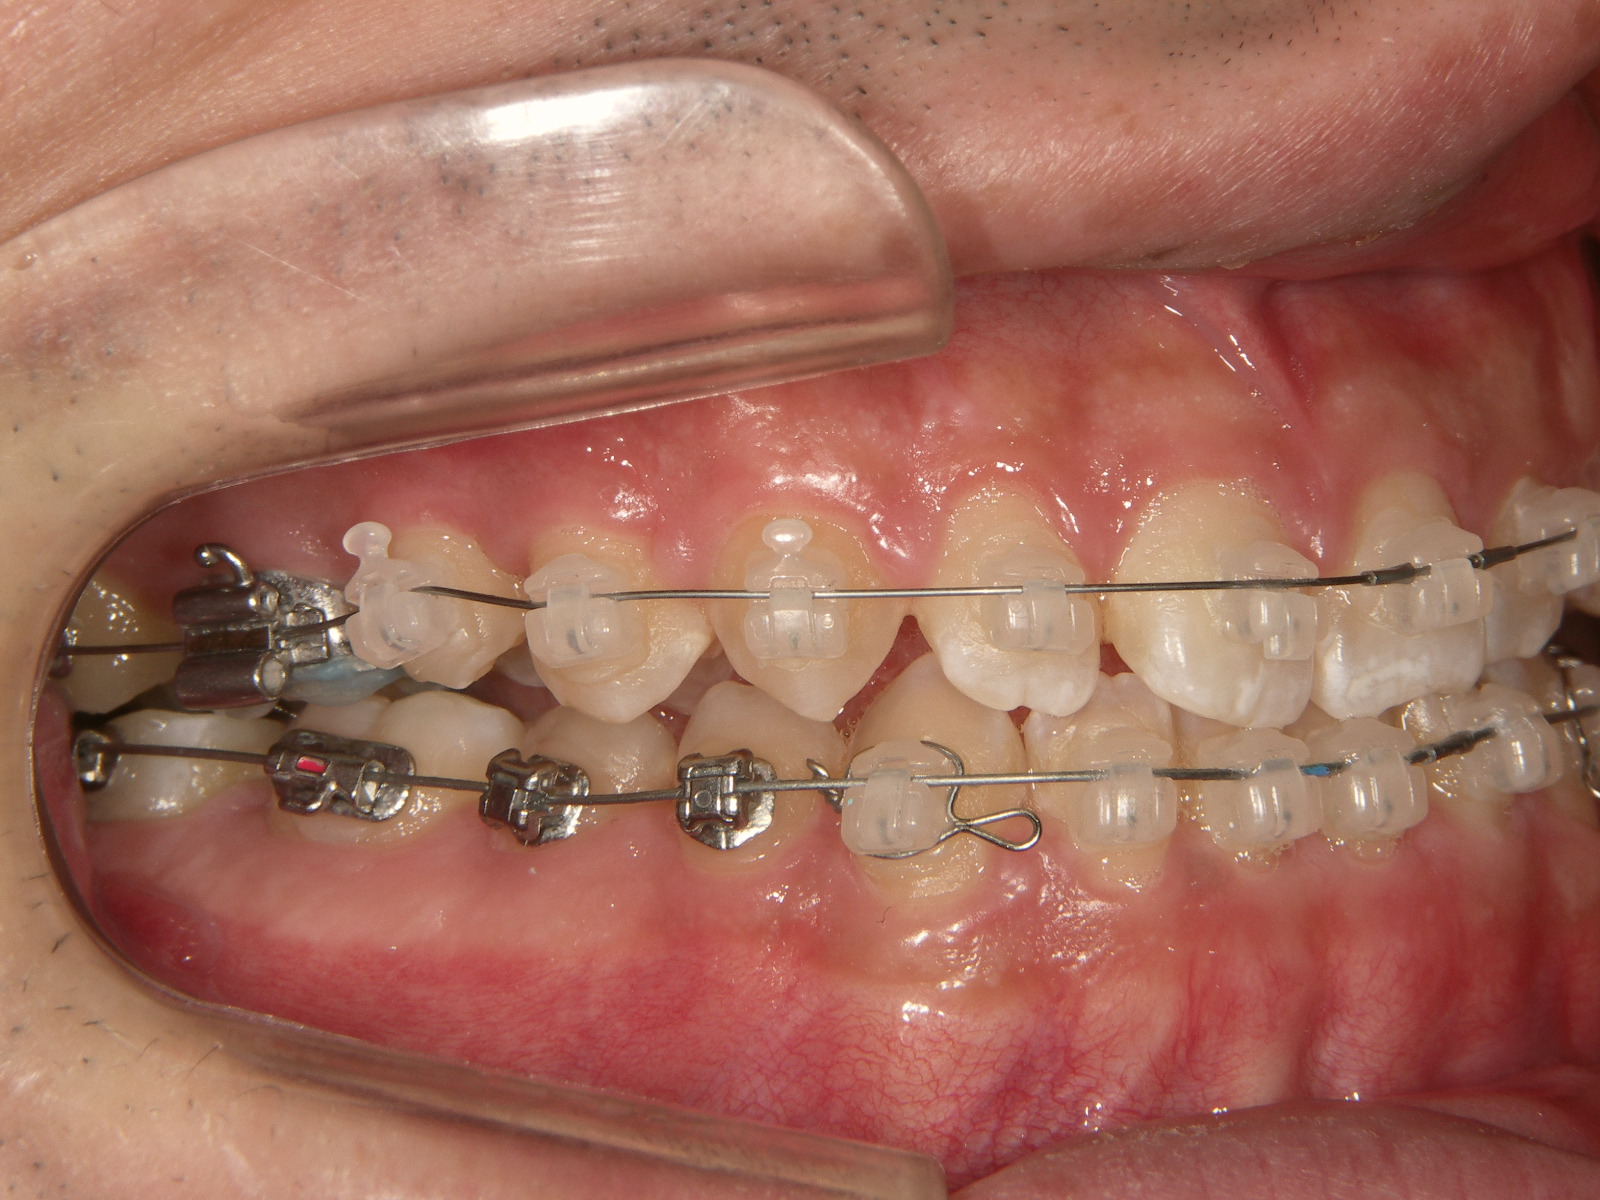

③矯正治療中

ブラケット矯正装置を装着し、上下のかみ合わせが正しい位置で合うように歯並びを調整します。